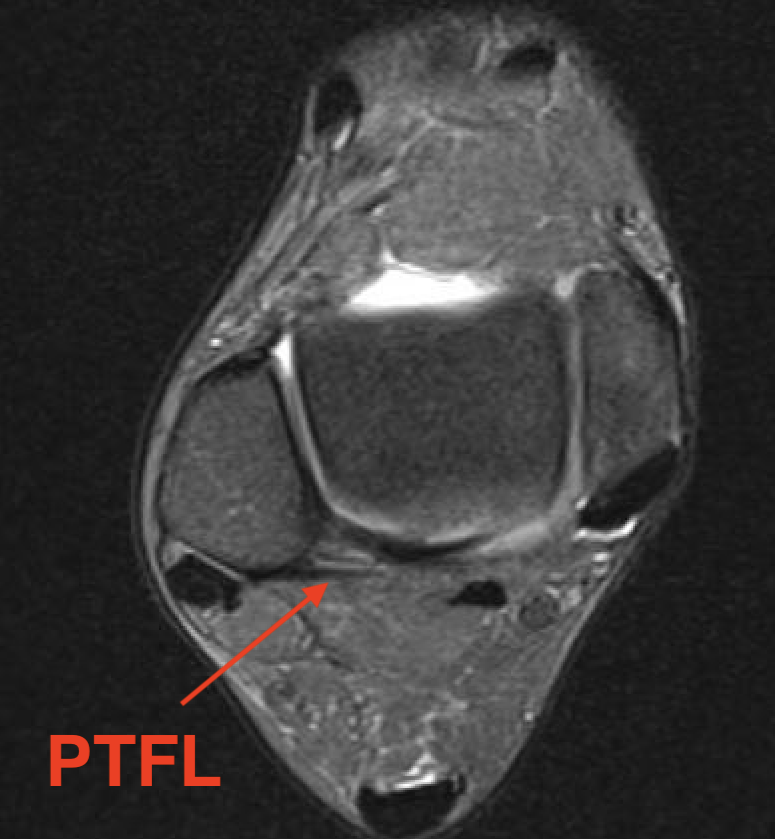

PTFL